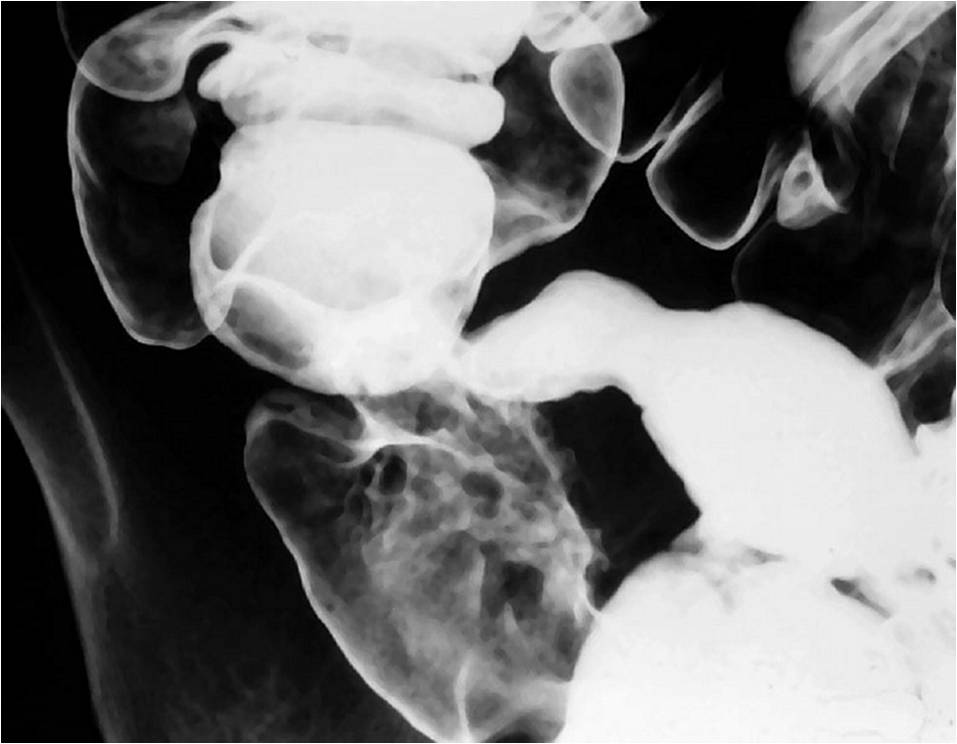

Рентгеноконтрастные Исследования Кишечника: Визуализация и Методики

Раздел: Иллюстрированный журнал